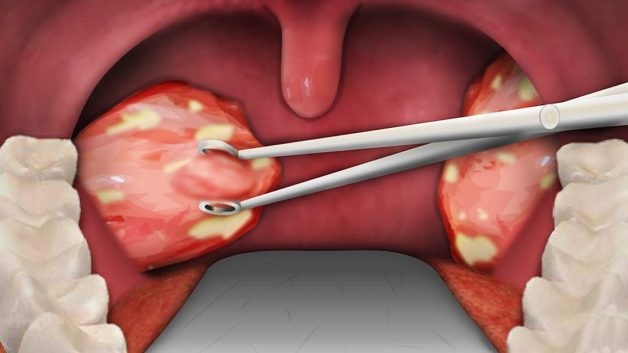

Hình ảnh mô phỏng amidan hốc mủ